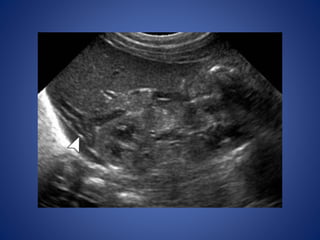

US image obtained in another healthy prepubertal girl shows small follicles within the ovaries

With the onsetof puberty, the influence of estrogen causes enlargement of the uterine fundus more than of the cervix, the uterus assumes the pear shape US image obtained in another healthy prepubertal girl shows small follicles within the ovaries